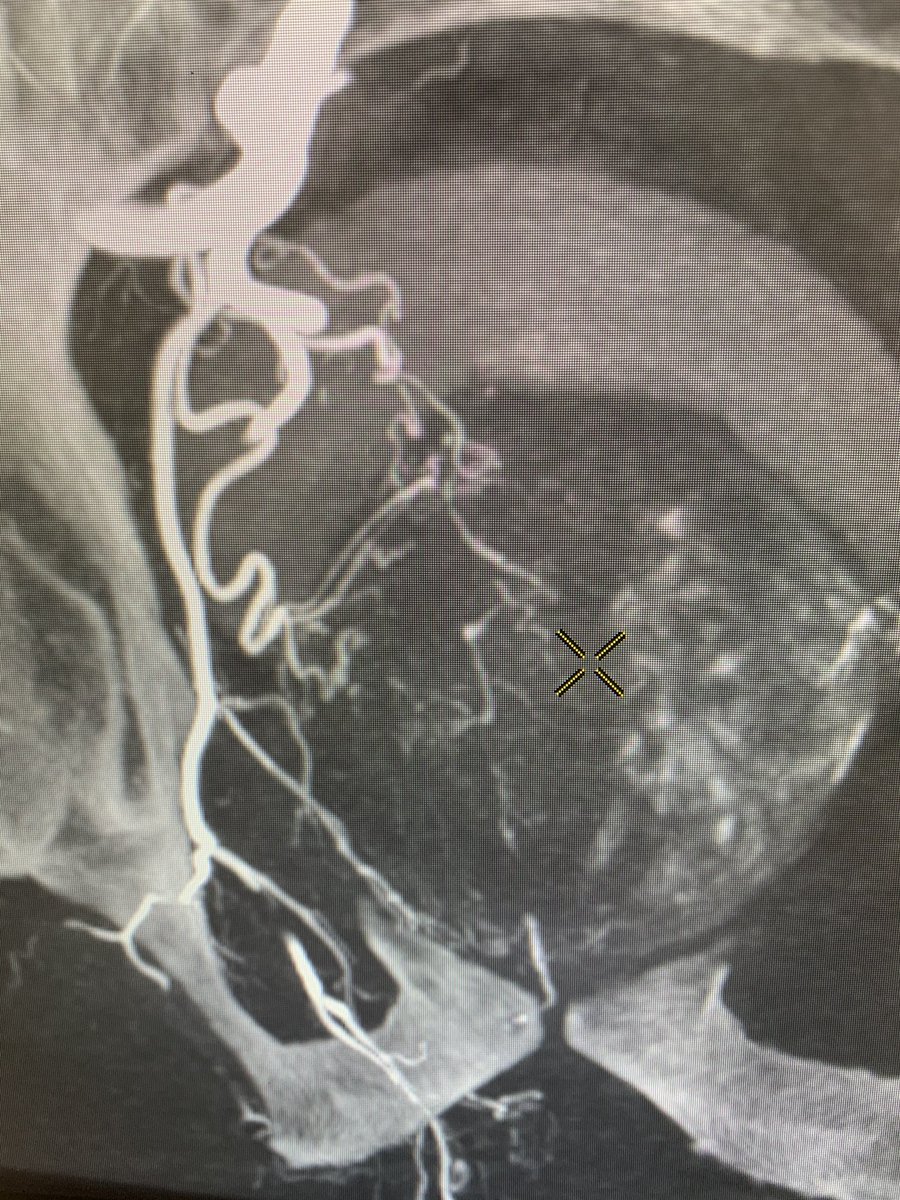

One of the trickier prostatic arteries to get into. Type 1 (joint origin with the superior vesical artery). But all you have to do is follow the red line...😉 @SIRRFS @StreamMeeting